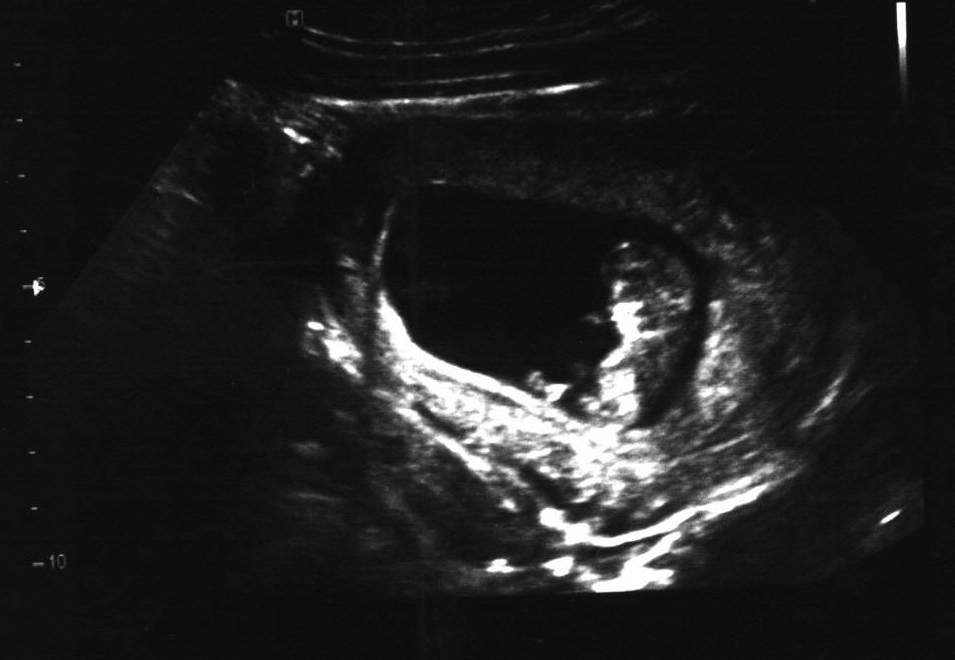

@littlemousecz Ahojda, sem si říkala kde se flákáš, že ani ty sem nepíšeš 😉 😉 Krásný, už to vypadá jako miminko, co? Ne jako ta tečka minule. 🙂 🙂 🙂 🙂 A je fajn, že je vše v pořádku. Za chvíli tě bude čekat prvotrimestrální screening, co?? 😉

@petrufa86 Ahojky. My teď vpráci máme hroznej fofr s plánem na příští rok, zítra má být hotovej a trochu jsme na to zapomněli 😀. Ale dneska jsem strávila dopoledne na gyndě, nalačno 😖 , takže mě je blbě doteďka, byla jsem objednaná na devátou, ale brali mě až v deset a krev až ve čtvrt na jedenáct, tak jsem docela trpěla, než jsem se mohla najíst. Ale vidět to miminko, to za to stálo. Byla jsem úplně unešená, jak se hýbalo, má sice jen 3,2 cm, ale na tý obrazovce vypadalo hrozně velký 🙂. Na screening jdu 4.9., tak to uteče jak voda. Vůbec to tak nějak utíká.... Nedávno jsem byla na IVF a teď už je to 10.týden.Akorát před kontrolou se to vždycky hrozně vleče, když se člověk bojí, aby mimi bylo v pořádku.Jinak je to krása.

@littlemousecz krásná fotečka, už to k něčemu vypadá. 😀 😀 😀

@martina_81 jj, už je poznat, že to bude človíček 🙂